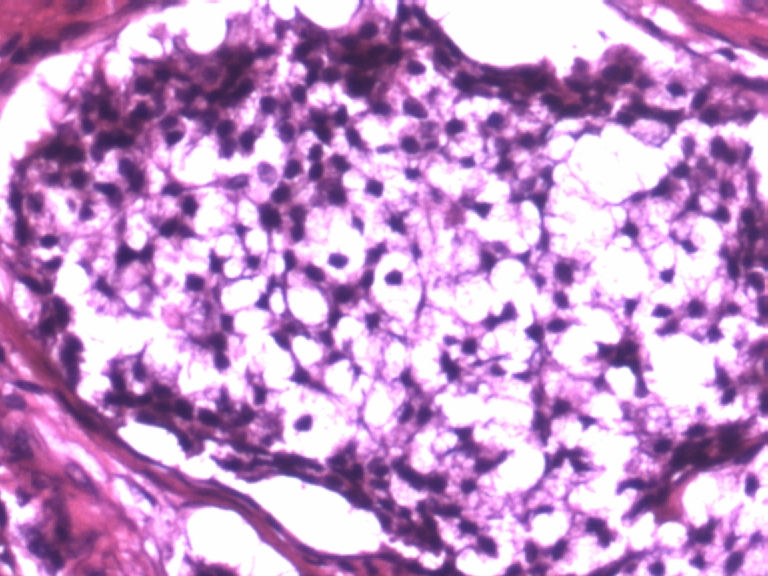

男,50岁,阑尾长7厘米,直径0.4---0.6厘米。剖开:尖端看见淡黄色区,不规则,界限欠清,0.15*0.2厘米,质中。

• 您看了吗?阑尾类癌?图3

图3

考虑阑尾类癌

像类癌,有些粘液,标记一下Syn、CgA,有可能是杯状细胞类癌

像粘液腺癌

按照胃肠胰腺神经内分泌肿瘤WHO2010分类,该例应属于NET G1(神经内分泌瘤,1级)。需标记Syn, CgA, Ki67.

倾向神经内分泌肿瘤,建议做CgA、SYN、Ki-67检查。